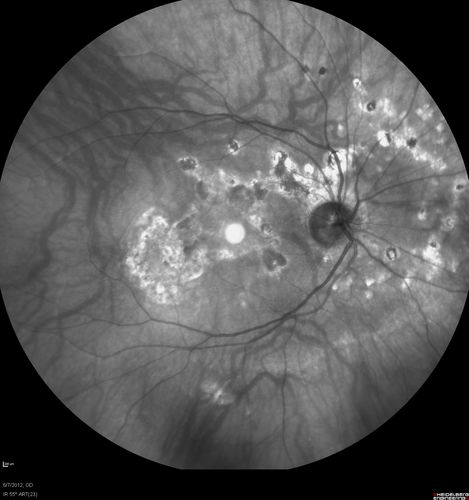

Punctate Inner Choroidopathy - Recurrent CNVM 4 years after initial treatment Left Eye

June 7, 2012.  This pleasant 35-year-old woman noticed decreasing vision in the left eye recently.   She returns now noticing the vision in the left eye is declining.   OD 20/50,  OS 20/80.  OS: Vertical C/D ratio is 0.3.  There is a scar just inferonasal to the fovea, which has grown some towards the fovea with a little blood just under the fovea.